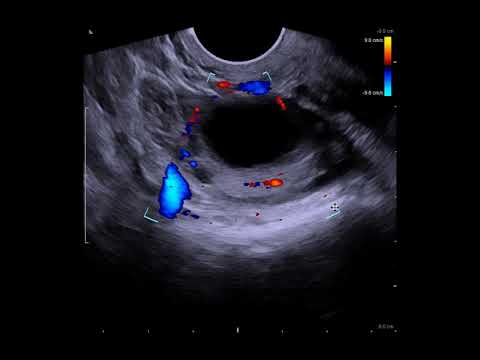

Если количество фолликулов в яичниках превышает 10, то это является отклонением от нормы. Обнаружить такую патологию можно при помощи внутривагинального УЗИ. Множественные фолликулы могут обнаружиться в любой период менструального цикла.

С начала менструального цикла в обоих яичниках образуется порядка 8-10 вторичных фолликулов. Примерно с восьмого или девятого дня цикла пузырьки начинают заполняться образующейся под воздействием синтезируемых женским организмом эстрогенов жидкостью. И уже на данном этапе заметен доминантный фолликул: он больше остальных, и это можно увидеть на УЗИ.

УЗИ-признаки доминанта

- визуализация фолликула размером 18 мм и больше;

- определение в нем яйценосного бугорка;

- утолщение слоя гранулезных клеток (теки);

После произошедшего выхода яйцеклетки в брюшную полость:

- уменьшение доминантного фолликула в размерах или полное его исчезновение при предшествующем обнаружении;

- свободная жидкость в позадиматочном пространстве;

Врач определит эхопризнаки доминантного фолликула в левом яичнике. Основной из них – визуальное определение фолликула с активно развивающейся внутри яйцеклеткой.

Его размер будет 18 мм или более, а слой гранулезных клеток заметно утолщен. Внутри такого «мешочка» специалист рассмотрит яйценосный бугорок. Если исследование проводилась сразу после выхода яйцеклетки, врач отметит признаки – уменьшение или исчезновение фолликула, появление жидкости позади матки.